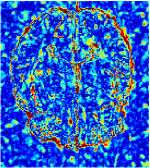

In this section, we test the generalizability of the proposed model that tests on unseen tasks. We fix the well-trained task-invariant parameter and only train for sampling ratios 15%, 25% and 35% with radio masks and sampling ratios 10%, 20%, 30% and 40% with Cartesian masks. In this experiment, we only used 100 training data for each CS ratio and apply a total of 50 epochs. The averaged evaluation values and standard deviations are listed in Table 5.4 and 5.4 for reconstructed T1 and T2 brain images respectively that proceed with radio masks, and Table 5.4 shows the qualitative performance for reconstructed T2 brain image that applied random Cartesian sampling masks. In T1 image reconstruction results, meta-learning improved 1.6921 dB in PSNR for 15% CS ratio, 1.6608 dB for 25% CS ratio, and 0.5764 dB for 35% comparing to the conventional method, which in the tendency that the level of reconstruction quality for lower CS ratios improved more than higher CS ratios. A similar trend happens in T2 reconstruction results with different sampling masks. The qualitative comparisons are illustrated in Figure 2, 4 and 5 for T1 and T2 images tested in skewed CS ratios in radio masks, and T2 images tested in Cartesian masks with regular CS ratios respectively. In the experiments that conducted with radio masks, meta-learning is superior to conventional learning especially at CS ratio 15%, one can observe that the detailed region in red boxes keeps edges and is more close to the true image, while conventional method reconstructions are hazier and lost details in some complicated tissue. The point-wise error map also indicates that Meta-learning has the ability to suppress noises.

Training with Cartesian masks is more difficult than radio masks, especially for conventional learning where the network is not very deep since the network only applied three convolutions each with four kernels. Table 5.4 indicates that the average performance of meta-learning improved about 1.87 dB comparing to conventional methods with T2 brain images. These results further demonstrate that meta-learning has the benefit of parameter efficiency, the performance is much better than conventional learning even if we apply a shallow network with small size of training data.